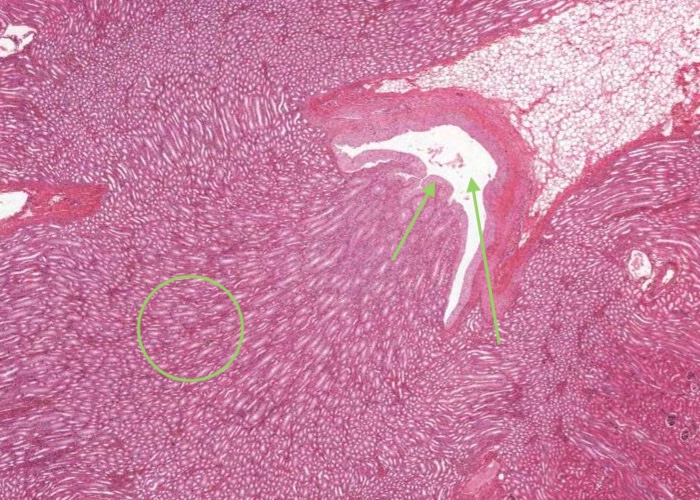

In most stained sections of kidney (including H&E), the medulla is the lighter stained inner region of the kidney. It contains straight tubules and collecting ducts with associated blood capillaries - the vasa recta. These tubules form conical shaped renal pyramids - their base faces the cortex and the apices open into a minor calyx through the tip of each pyramid (renal papilla). Pyramids are separated by extensions of the cortex (renal columns).

A renal pyramid is a conical structure in the medulla formed by the tubules. Humans may have 8-12 pyramids. The base of the pyramid faces the cortex and the apex (papilla) projects into the minor calyx

The renal papilla is the tip of each pyramid. The indented epithelial surface at the tip of the papilla (area cribosa) may represent the merging of collecting ducts to form a papillary duct (duct of Bellini) that empties urine into the minor calyx. The collecting ducts are wider in diameter and will exhibit epithelium with increasing numbers of columnar cells.